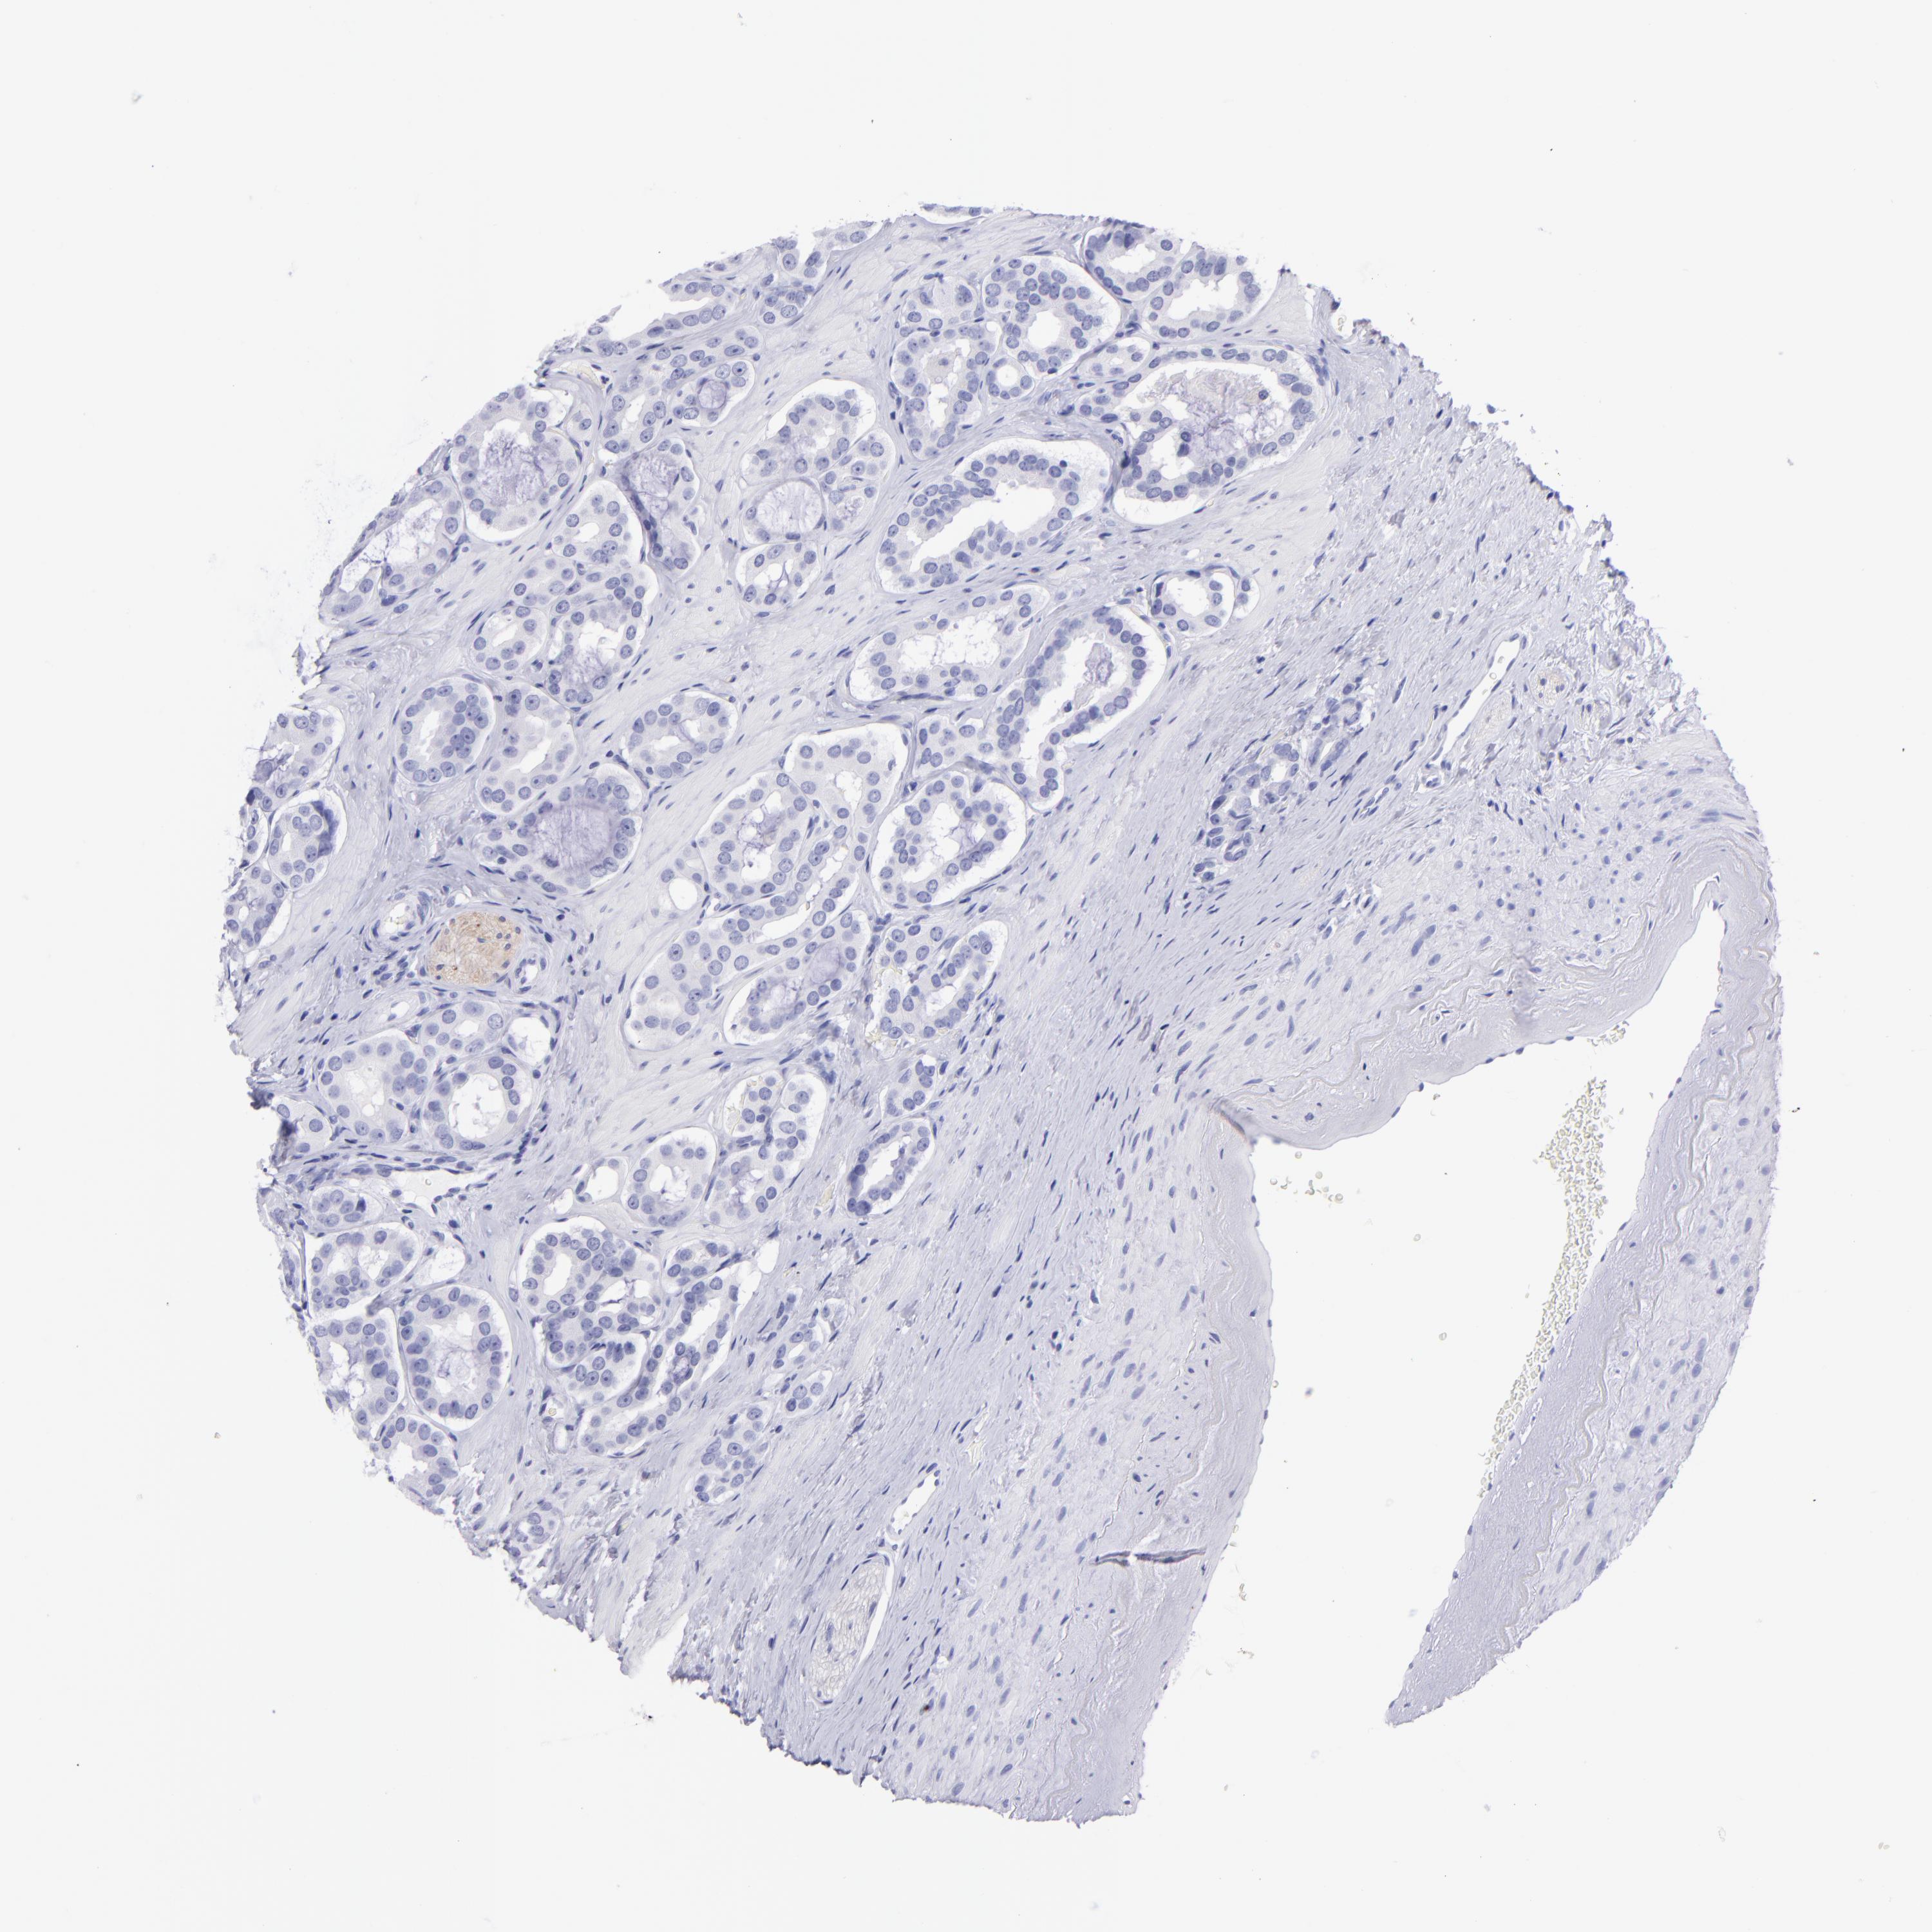

PROSTATE CANCER - Protein expressioni

A mouse-over function shows sample information and annotation data. Click on an image to view it in a full screen mode. Samples can be filtered based on level of antibody staining by selecting one or several of the following categories: high, medium, low and not detected. The assay and annotation is described here.

Antibody stainingi

Antibody staining in the annotated cell types in the current human tissue is reported as not detected, low, medium, or high, based on conventional immunohistochemistry profiling in selected tissues. This score is based on the combination of the staining intensity and fraction of stained cells.

Each image is clickable and will lead to virtual microscopy that enables deeper exploration of all samples and also displays staining intensity scores, fraction scores and subcellular localization as well as patient and tissue information for each sample.

HPA023266

HPA023278

HPA023280

HPA023338

CAB002672

Staining

High

Medium

Low

Not detected

Intensity

Strong

Moderate

Weak

Negative

Quantity

>75%

75%-25%

<25%

None

Location

Nuclear

Cytoplasmic/membranous

Cytoplasmic/membranous,nuclear

Adenocarcinoma, High grade

Adenocarcinoma, Low grade

Adenocarcinoma, NOS

Adenocarcinoma, Medium grade